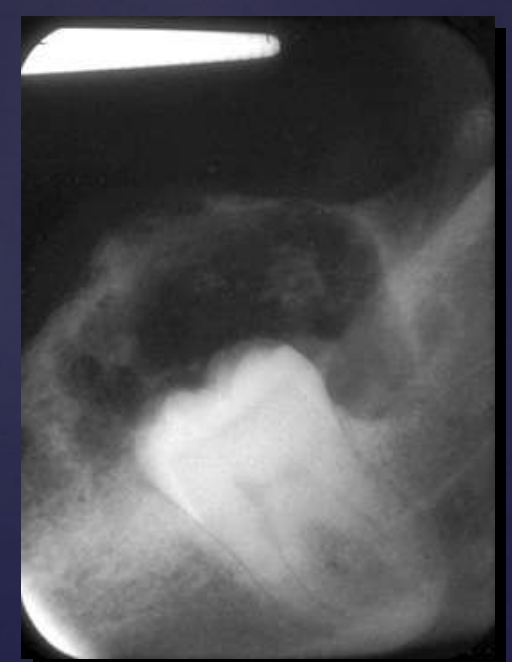

how do ameloblastomas radiographically present?

well circumscribed, corticated

radiolucent

unilocular/multilocular (coarse/curved septae)

expansile

Tooth displacement/root resorption

ameloblastoma

Pericoronal/mural; impacted tooth

Displacement of #32

Osseous expansion

Thinning of cortices

Displacement of inferior alveolar nerve canal